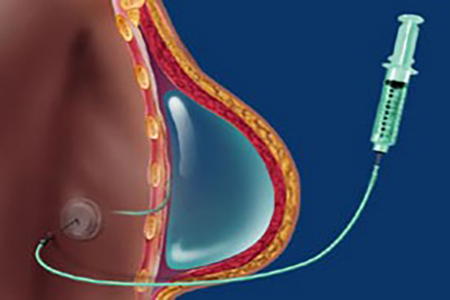

بزرگ کردن سینه با تزریق یک روش عالی و طبیعی به منظور بهبود اندازه و شکل سینهها است و نیازی به انجام یک عمل جراحی عمده ندارد. با این روش از هیچ پروتز سینهای استفاده نمیشود، نیازی به بیهوشی عمومی، بخیه، آرام بخش داخل وریدی و بهبودی طولانی مدت نیز نمیباشد. دو گزینه تزریق محبوب شامل تزریق چربی و ژل وجود دارند.

اساساً در تزریق چربی، چربی از ناحیهای از بدن (معمولاً باسن و ران) گرفته شده و به منظور حجم دادن به سینه در این ناحیه تزریق میشود. چربی برداشته، فرآوری و سپس با دقت تزریق میشود.

بزرگ کردن سینه با تزریق چربی شامل دو فرایند است که به طور همزمان انجام میشوند، لیپوساکشن، که برداشت سلولهای چربی را ممکن میسازد، و انتقال چربی که در آن چربی برداشته شده با دقت آماده میشود و سپس به سینهها انتقال داده میشود. نواحی چربی اضافه که ممکن است شامل قسمت بیرونی یا داخلی رانها، شکم، ناحیهی کمر و دیگر نواحی باشند بررسی شده و نواحی که در انتقال چربی بیشترین نقش را داشته و موجب خوش تراش شدن بدن میشوند، شناسایی خواهند شد. بنابراین مزیت تزریق چربی اتولوگ و انتقال آن به سینه دو مورد می باشد، یعنی در صورت لزوم شامل خوش فرم کردن ناحیه اهداکننده نیز خواهد شد. برداشتن چربی با استفاده از تکنیکهای لیپوساکشن از طریق سوزنهای کوچک انجام میشود. فرایند تزریق چربی نیاز به تکنیک ظریفی جهت انتقال سلولها به لایههای متعدد سینه جهت دستیابی به بهترین نتایج ممکن دارد.

یک سرنگ پر از ژل انتخابی به نواحی مورد نظر در سینهها و معمولاً در بالای سینه و طرفین آن تزریق میشود. جهت جلوه بیشتر میتوان ژل را در نزدیکی عضلات سینه تزریق کرد که باعث لیفت سینه میگردد. برای پرتر نشان دادن سینهها نیز میتوان ژل را در بالای سینهها تزریق نمود.